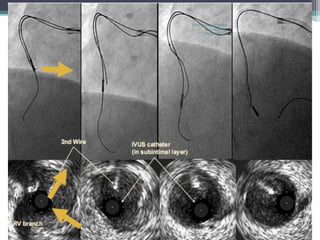

IVUS Navigated Wiring

IVUS – Depict cross sectional view of coronary tree

IVUS focus on plaque distribution, calcification, reference vessel size &

side branch anatomy

Applicability of IVUS in CTO PCI

1)Side branch method to navigate CTO wire into true lumen from

proximal cap

2)Subintimal rentry from the proximal true lumen

IVUS guided subintimal rentry – Last resort for getting a subintimal wire

into distal true lumen

Applicable even after losing site of distal vascular bed on angio

•1.5-2mm baloon dilatation in presumed subintimal space

•IVUS is advanced into the space monitored to orient 2nd wire to

true lumen

Key points

a) Ability to translate cross sectional image into 3D needed

b) 2nd stiff tapered wire over micro catheter - 8f guide mandatory

c) Reentry point should be closer to proximal cap

d) Contrast injection should be withheld esp after small ballon

dilatation